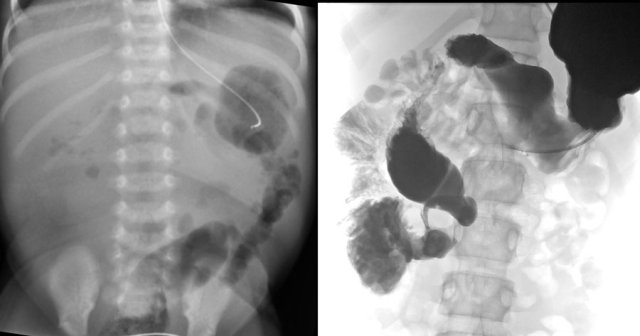

Ileal atresia

As with jejunal atresia, ileal atresia results from an in utero ischemic event.

More atretic foci can be present simultaneously, but the distal ileum is the most common site to be involved.

Radiographs will show multiple dilated bowel loops and absence of air in the colon as seen on the image on the left.

A colon enema will show a microcolon with contrast filling ending blind in the ileum (arrow on image on the right).